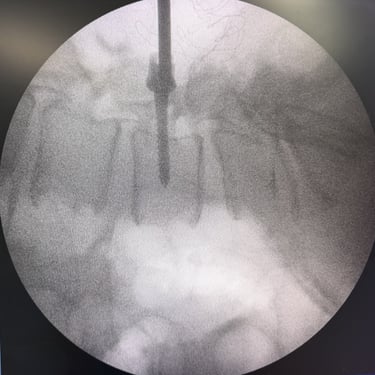

La listesis L4–L5 asociada a estenosis lumbar severa se caracteriza por el deslizamiento vertebral y el estrechamiento del canal espinal, generando dolor lumbar, claudicación neurogénica y compromiso radicular. Cuando el tratamiento conservador no logra un control adecuado de los síntomas, la fijación transpedicular (FTP) asociada a la fusión intersomática transforaminal (TLIF) constituye una alternativa quirúrgica eficaz. Este procedimiento permite descomprimir las estructuras nerviosas, restaurar la alineación vertebral y proporcionar una estabilización sólida del segmento afectado, favoreciendo una recuperación funcional segura y una mejor calidad de vida.